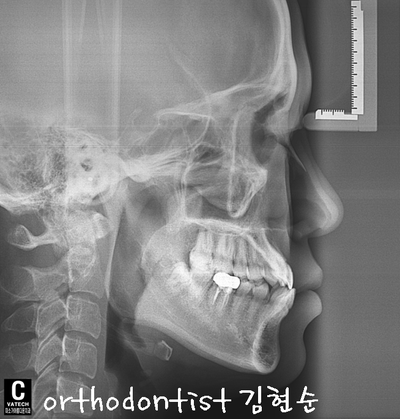

반대 교합 -

교정 문의 환자 : 김 0 0

나이 : 24 세 F / 환자분 소개

교정 사유 : 반대 교합 / 치아 중심선 / 주걱턱

아래 환자분의 증례를 통해 알아보겠습니다

- 일단 치열이 고르지 못합니다 사이사이 공간도 벌어져 보입니다 ..

- 아래 치아가 윗니보다 나와 보이고 턱도 돌출 모습을 보이고 있습니다

- 정면에선 치아 중심선, 가운데 라인이 맞지 않습니다

- 흔히 말하는 반대 교합을 보이고 있습니다

- 중간중간 벌어짐과 틈새가 보입니다

- 위/아래 사진으로 옆모습 벌어진 간격이 넓습니다;;...

- E - LINE 보면 아래턱과 입술이 돌출된 모습을 확인할 수 있습니다